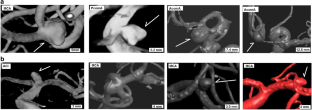

Supplemental Figure 1

Localization of ruptured and unruptured aneurysms (PNG 65.8 kb)